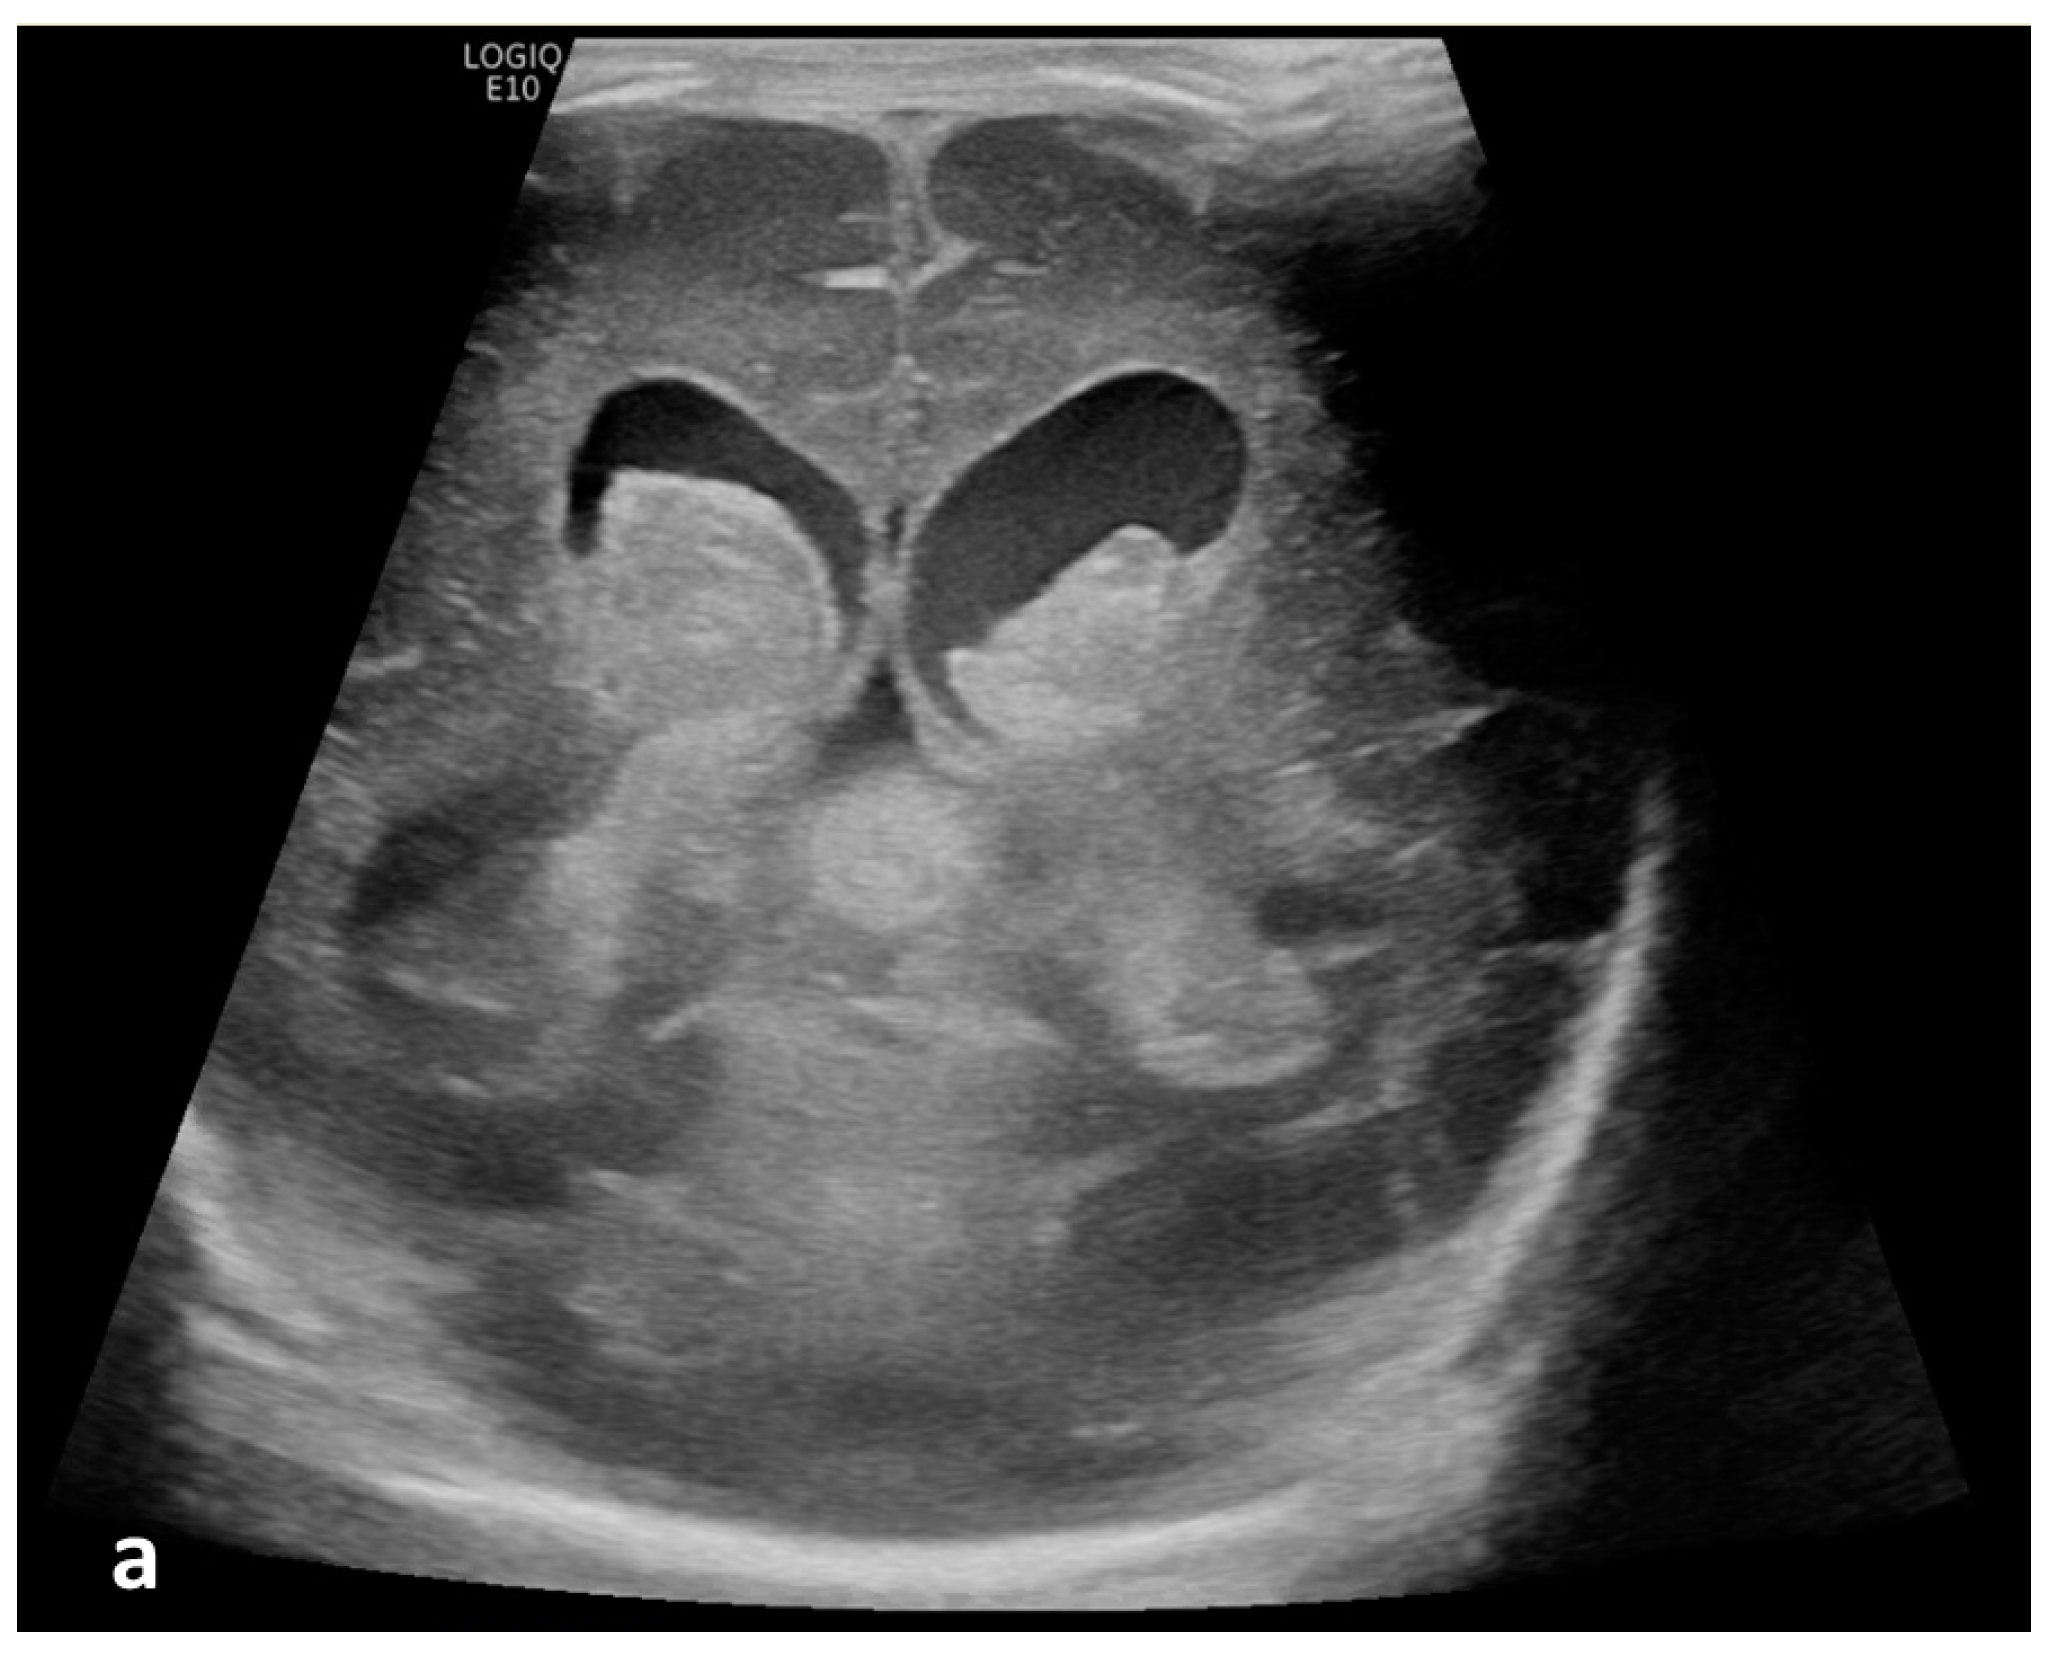

Figure 2.

Cerebrospinal fluid (CSF) flow visualized in a patient with post-hemorrhagic hydrocephalus. A 7-day-old boy with a history of severe intraventricular hemorrhage and ventriculomegaly. Coronal and sagittal grayscale ultrasound shows enlargement in the lateral and third ventricles, as well as evolving choroid plexus hemorrhage and fine granular mobile debris in the ventricles (a–c). The parenchymal evaluation shows grade IV left parieto-occipital periventricular hemorrhage (c). Sagittal B-Flow (d–f) demonstrates turbulent caudocranial CSF flow from the cerebral aqueduct (arrows) into the third ventricle (dotted arrows). The entire clip is provided as Supplemental Material S2.